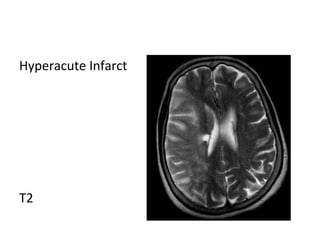

Hyperacute Infarct

T2